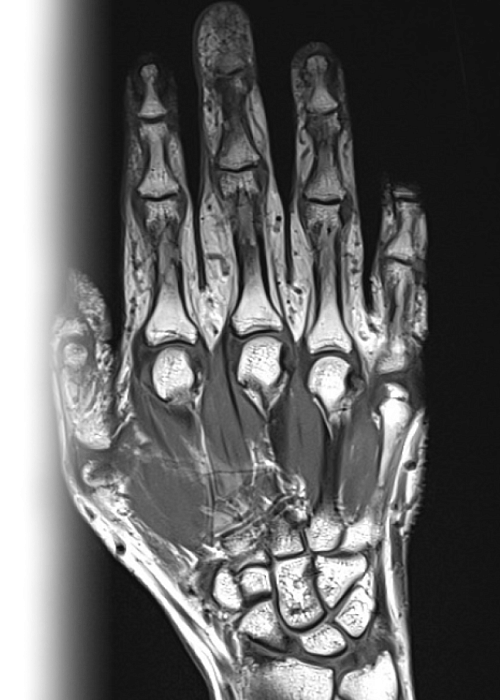

МРТ кисти МРТ кисти

МРТ кисти

Магнитно-резонансная томография кисти – важный метод исследования, который позволяет оценить состояние кисти.